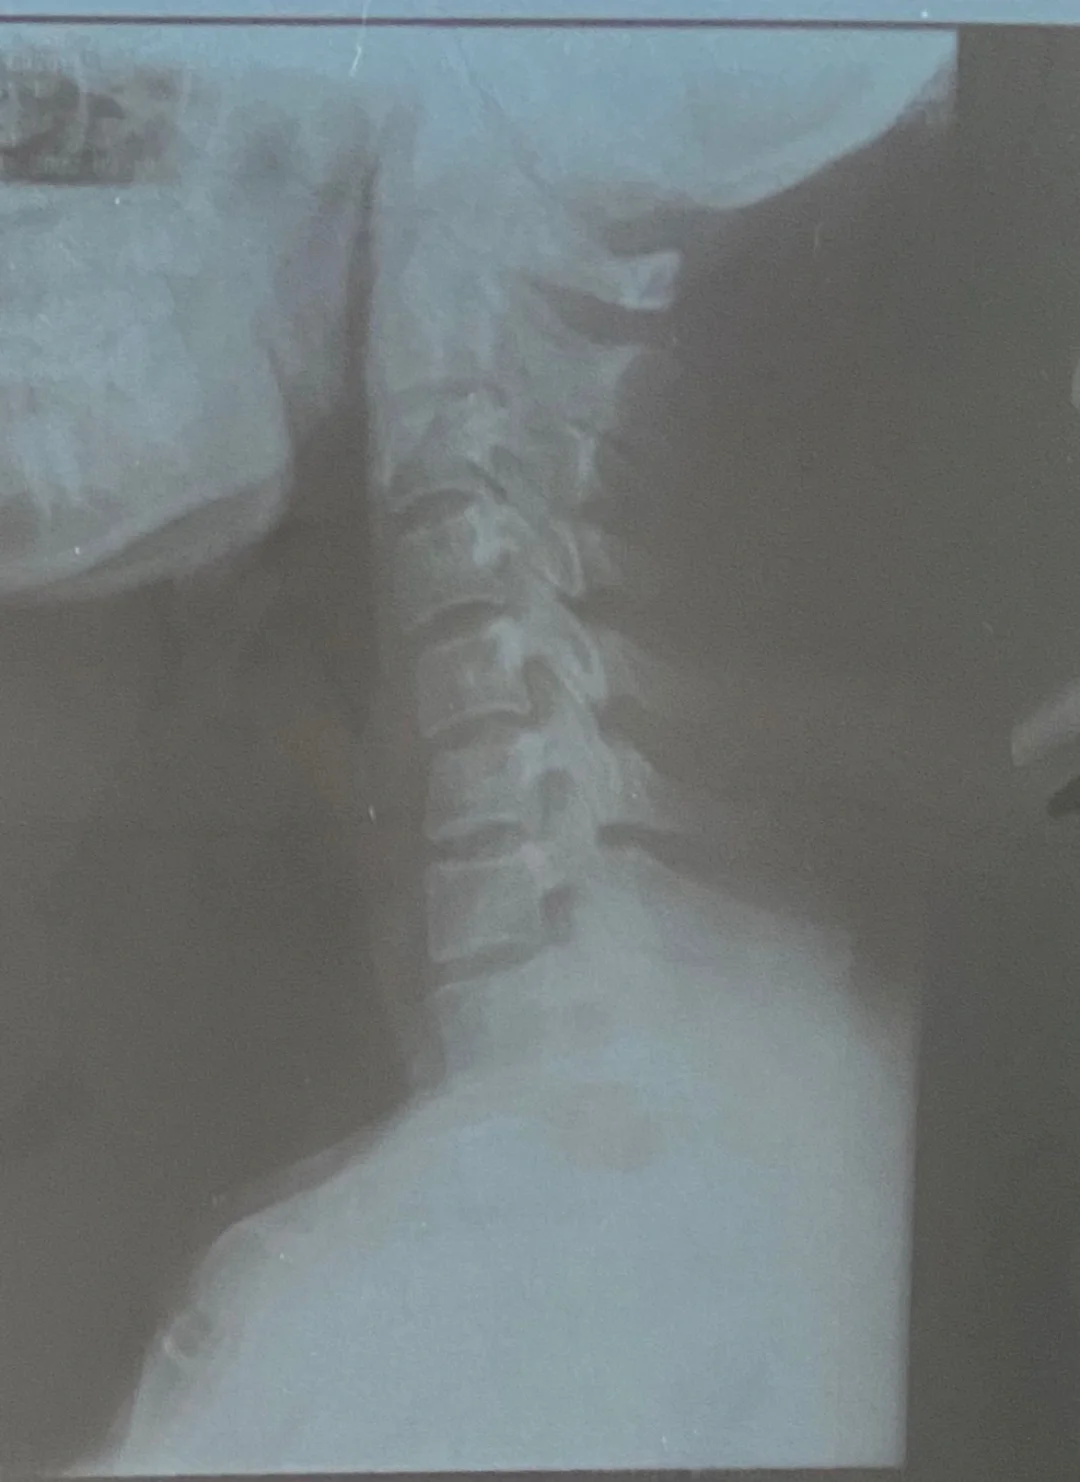

颈椎生理曲度变直后通常可以恢复,但恢复程度因人而异,需结合病因治疗方式及日常护理综合干预一恢复的可能性与影响因素颈椎生理曲度变直是颈椎退行性改变的常见表现,多由长期低头颈部外伤颈椎疾病如间盘突出管狭窄或遗传发育因素导致轻度变直通过干预可部分或完全恢复,但严重变直或合并。

若颈椎变直的时间较长程度较重,颈椎的生理曲度可能因长期力学失衡发生结构性改变,如椎间盘退变骨质增生等,此时恢复原状较为困难但通过规范治疗如牵引针灸药物治疗和康复训练,仍可缓解症状延缓病情进展,并预防进一步恶化颈椎变直常伴随颈肩部疼痛酸胀或头晕等症状,需及时干预1。